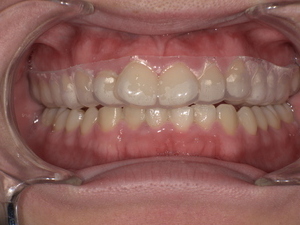

【症例紹介】20代女性|歯ぎしり改善で生活の質が向上

初診時の状態

患者様は

「歯ぎしりの音が気になる」

「歯がすり減っている」

というお悩みで来院されました。

診察の結果、

👉 歯の表面が平らに摩耗

👉 象牙質の露出

👉 咬筋の過緊張

といった典型的な歯ぎしりの所見が確認されました。